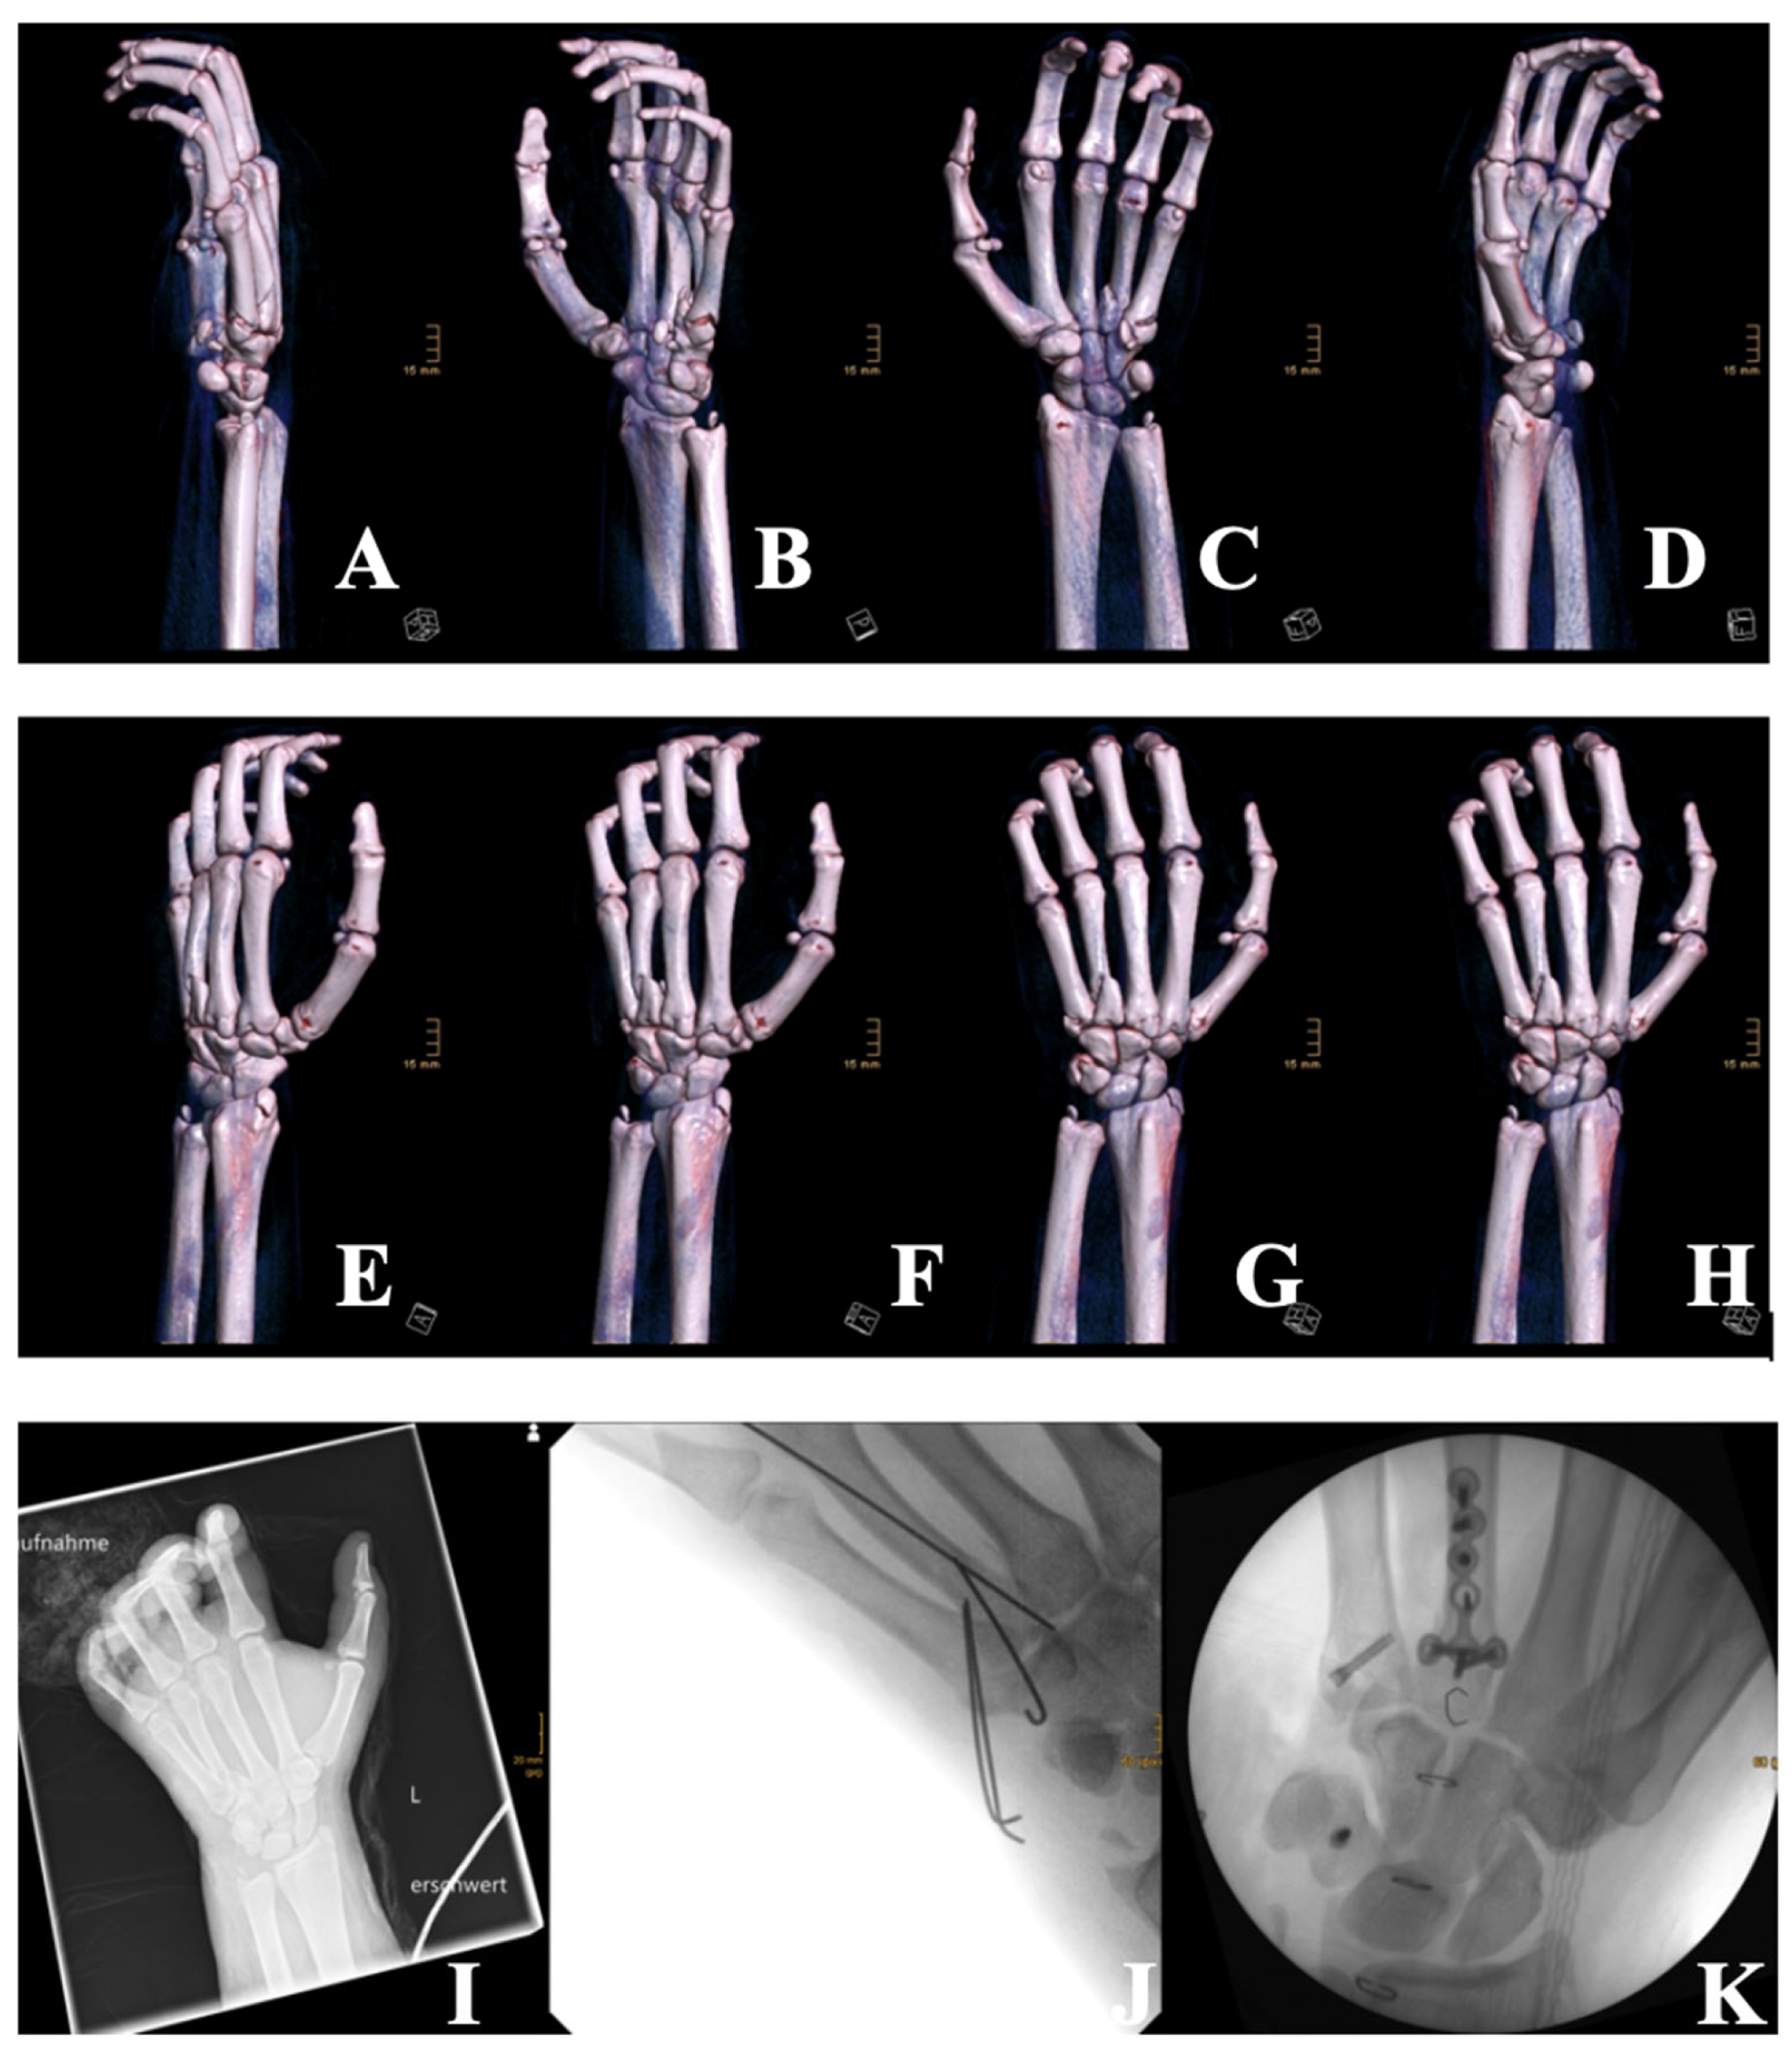

Figure 2. Three-dimensional CT reconstructions (AH) taken at the time of admission and showing multiple fractures of the left hand, including metacarpal fractures (3rd, 4th, and 5th), a triquetrum fracture, a hamate fracture, and fractures of the radial and ulnar styloid processes. Extensive soft-tissue damage is also visible. (I): X-ray imaging of the left hand upon admission, which confirmed multiple intra-articular and styloid fractures. (J): Postoperative radiograph following temporary stabilization with K-wires of the metacarpal bones 4 and 5 due to extensive swelling and soft-tissue trauma. (K): Intraoperative fluoroscopic image after revision surgery on 16 January 2025, showing final osteosynthesis with plates and screws for the metacarpals, and triquetrum fixation using the Aptus® 2.0 system.

The patient was resuscitated according to Advanced Trauma Life Support (ATLS) protocols. He received 2.5 L of crystalloid intravenous fluids and analgesia, and his wounds were covered with sterile dressings. After approximately two hours of primary stabilization at the initial hospital, the patient was transferred to our facility within the following hour. Upon arrival, he underwent secondary trauma assessment in the resuscitation bay, including urgent laboratory testing and imaging. Imaging revealed multiple fractures in the hand but no additional injuries (Figure 2). A cranial CT scan, performed due to the facial involvement, showed no intracranial bleeding or skull fractures, but revealed small, shell-like avulsion fragments at the left processus nasalis of the maxilla, as well as a diffuse galea hematoma with bifrontal and periorbital distribution, which was more pronounced on the left side. Additional hematoma formation was seen around the nose and in the left ventrolateral midface/maxillary region. The ophthalmology consult revealed no corneal or intraocular damage. A clinical neurological assessment also found no evidence of traumatic brain injury, and no further imaging was deemed necessary. Due to the severity of his burn injuries, he was emergently transferred to the severe burn intensive care unit for further management. Despite the administration of high-dose analgesia, the patient remained in severe pain. Due to the presence of circumferential burns on his left forearm, and in order to prevent subcutaneous compartment syndrome, early intervention with enzymatic debridement using Nexobrid® was performed. However, progressive swelling and emerging sensory deficits in the fingers persisted despite sufficient eschar debridement, necessitating emergency surgery for compartment release. The patient subsequently underwent fasciotomy with carpal tunnel and Loge de Guyon decompression to relieve pressure and restore circulation. Although an open fracture was present, we actively decided against immediate osteosynthesis due to the massive swelling. Antibiotic therapy was initiated, but we opted to allow the hand to decongest first before considering the placement of hardware, which could have further compromised wound closure. Additionally, dermotraction was performed on the left hand after compartment release using medical skin staples and an elastic band to maintain tissue alignment and prevent retraction of tissue. Two days later, on 3 January 2025, the patient underwent a tangential necrosectomy of the nose to remove devitalized tissue, followed by application of an Epicite® mask for advanced wound care. Further surgical intervention was carried out on 8 January 2025, including temporary K-wire osteosynthesis of metacarpal bones 4 and 5, along with tangential necrosectomy and debridement of necrotic tissue. Due to severe soft-tissue swelling, K-wires were used as an initial stabilization method to allow for soft-tissue recovery prior to definitive fixation. A split-thickness skin graft was harvested from the left thigh, measuring 10 × 7 cm (70 cm2) with a thickness of 0.2 mm, and applied to the burned areas of the left hand. The graft was meshed at a 1:1.5 ratio to facilitate drainage and flexibility. To promote optimal healing, the wound edges were carefully debrided and padding dressings were applied.

On 16 January 2025, a revision surgery was necessary due to the complexity of his fractures. This involved plate and screw osteosynthesis for metacarpal bones 4 and 5, as well as triquetrum fixation using an Aptus® 2.0 system to stabilize the wrist. Throughout his hospital stay, the patient received antimicrobial therapy with Cefazolin, administered from 1 January to 8 January 2025, and again from 17 January to 20 January 2025, to prevent infection. The patient remained hospitalized for a total of 20 days, undergoing intensive physiotherapy to restore hand mobility and prevent contractures. His pain was effectively managed with an axillary plexus catheter and systemic analgesia. By the second week, he was successfully mobilized to standing and walking without complications. Upon removal of his dressings, the split-thickness skin grafts were found to be well-adhered, with only minor scarring. Despite the severity of his injuries, the patient remained fully aware of his condition and actively engaged in his rehabilitation process. His cooperation and psychological resilience contributed significantly to his recovery. He returned to work 13 weeks after the injury. Currently, the patient shows early signs of hypertrophic scarring, particularly on the dorsum of the left hand. Depending on the further course, a corrective procedure, such as Z-plasty or medical needling, may become necessary to improve scar pliability and functional outcomes. The injury, however, highlights the devastating consequences of firework-related trauma, particularly when high-explosive, illegal pyrotechnics are involved. The total hospital costs for this patient’s treatment amounted to €58,459.52, as calculated according to the standardized German DRG (diagnosis-related groups) reimbursement system, which reflects the level of clinical complexity and required resource utilization in each case [10].